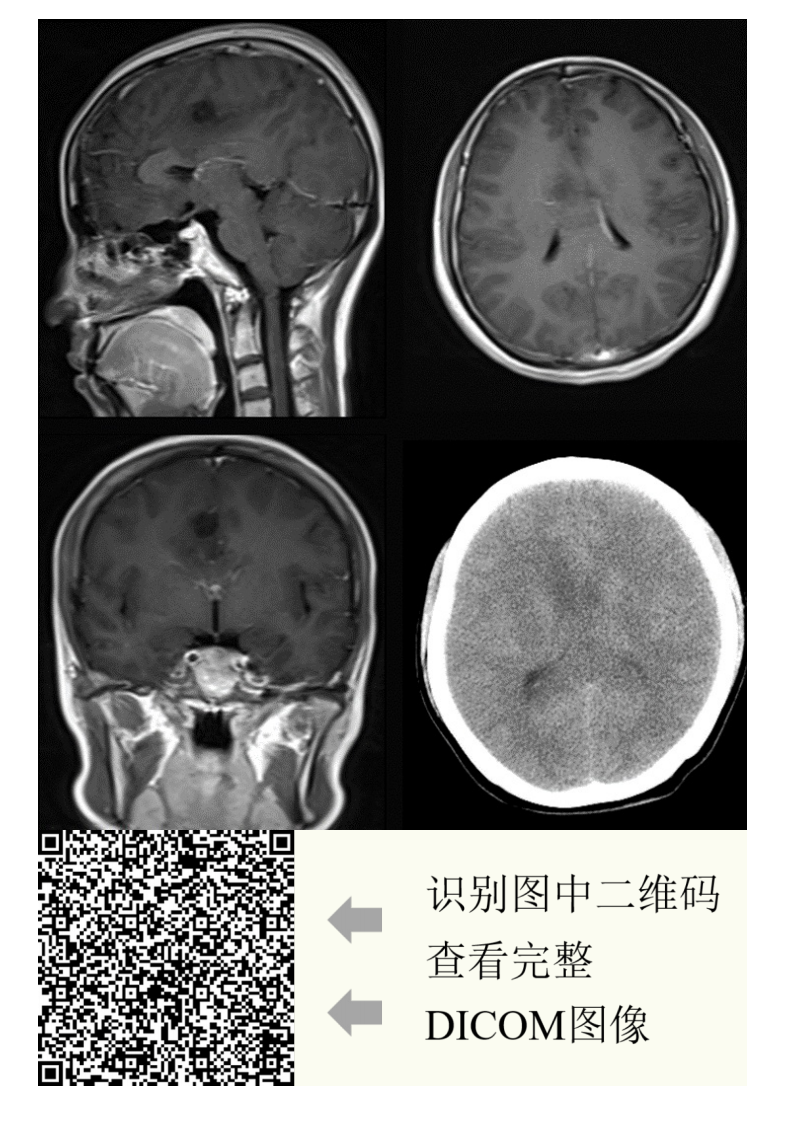

中大放射

20210608_2【晨读结果公布】2021.06.07神经系统疾病——病例1:间变型少突胶质细胞瘤;病例2:PCNSL;病例3:胼胝体急性梗死.pdf